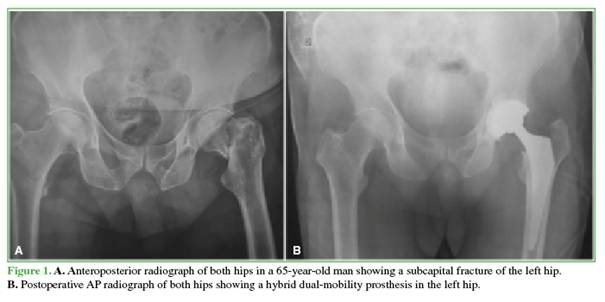

A descriptive, retrospective study was conducted, reporting preliminary results at 2 years of follow-up, in a series of patients treated with primary THA using a dual-mobility cup at a single center (a tertiary-care institution in the public health system of the Autonomous City of Buenos Aires) between January 2014 and December 2019 (Figures 1 and 2).

A total of 61 patients (30 women and 31 men) underwent THA with a dual-mobility acetabular cup system [cemented, n = 17 (27.9%); hybrid, n = 10 (16.4%); uncemented, n = 34 (55.7%)]. The mean age was 62.5 years. The following underlying conditions were recorded: hip osteoarthritis (36 cases, 59%), subcapital hip fracture (17 cases, 27.9%), and avascular necrosis of the hip (8 cases, 13.1%). Demographic characteristics are shown in Table 1.